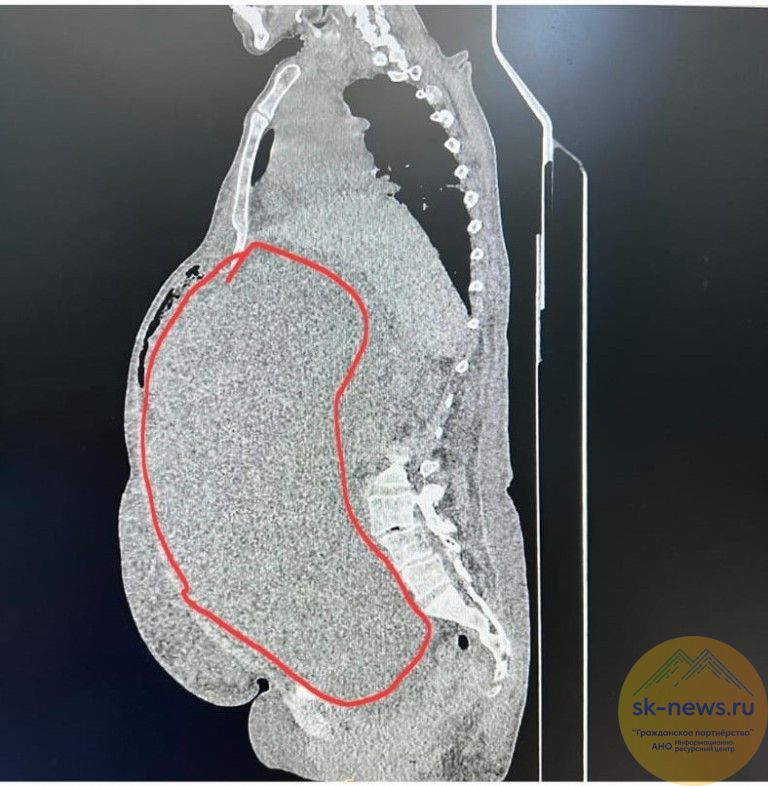

Женщина обратилась за помощью в поликлинику по месту жительства, где выявили объемное образование малого таза и брюшной полости. Пациентку направили на консультацию в поликлинику Ставропольского онкодиспансера. Компьютерная томография брюшной полости и малого таза показала гигантскую опухоль с локализацией слева до уровня малого таза с компрессией петель кишечника, смещением левой почки в поясничный отдел, четкими контурами, негомогенной структуры. Онкомаркеры также были повышены – СА 125 при норме 0-35 Ед/мл составлял 70,5 Ед/мл; НЕ-4 при норме 0-76,2 Пмоль/л был равен 83,2-Пмоль/л).